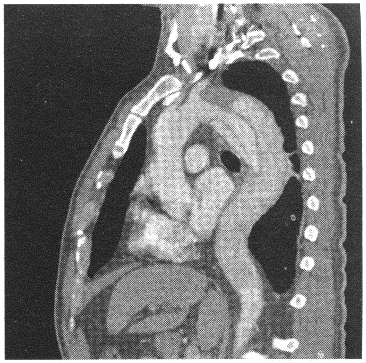

患者,女性,50岁。胸背部疼痛1天余。查体:呼吸音减弱。胸部CT强化如图。![]() |

| 19.CT图片显示的征象包括 |

| 20.最可能的CT诊断是 |

| 21.显示主动脉夹层破口位置的最佳CT后处理方法是 |

| 正确答案:19.CDF;20.B;21.C |